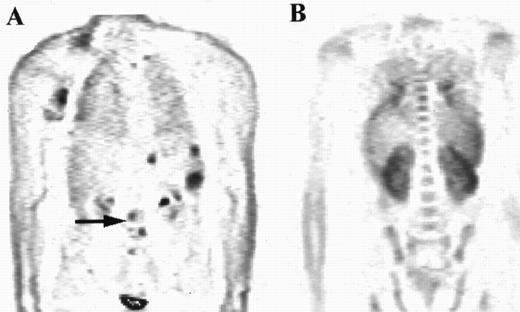

For the purposes of this study, the intensity and distribution of FDG activity within the marrow was visually scored by three nuclear medicine physicians independently. The marrow was assumed to be abnormal where the uptake was equal to or greater than uptake into the liver, provided the liver uptake was greater than background. In one patient where there was negligible uptake within the liver, marrow uptake was compared to uptake within soft tissue rather than using the liver as the reference organ. The pattern of increased uptake was also noted, with patients who appeared to have focal disease only within the marrow differentiated from those with diffusely abnormal marrow changes. Representative examples of cases with marrow uptake of differing intensity (Fig 1) and distribution (Fig 2) are shown.

The distribution of uptake within the marrow was noted. Focal abnormality is seen within the lumbar spine in patient A (arrow), while patient B has diffuse marrow abnormalities.

All four patients who had focal marrow disease on the PET scan but histologically normal iliac crest marrow had normal FDG uptake at the site of the biopsy. In that respect these patients could be classed as concordant. In one of these patients subsequent biopsy of a “hot spot” localized within the left humeral head confirmed nodular sclerosing HD in the marrow (Fig 4). The other 3 patients did not have additional biopsies, but the 2 patients with high-grade NHL had other evidence of stage IV disease, with pulmonary lymphoma deposits shown by PET and CT.

PET images of a patient with areas of focal increased uptake in marrow, most notably in the left humerus (solid arrow, A) and in the thoracic spine (B). The marrow was not diffusely abnormal and much of the axial skeleton exhibited FDG uptake less than in liver (broken arrow).